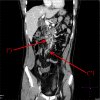

A 34-year-old man presented to our hospital with a 5-day history of progressive abdominal pain and fever. A CT scan identified extensive mesenteric lymphadenopathy. Initial diagnostic tests were inconclusive. Abdominal lymph node biopsy showed histiocytic necrotising lymphadenitis, compatible with Kikuchi-Fujimoto disease (KFD). This benign and self-limiting disease generally resolves following supportive treatment. In this case, remission occurred within 3 weeks of initial presentation. KFD is a very uncommon cause of lymphadenopathy, and selective mesenteric involvement is rare. Definitive diagnosis often requires lymph node biopsy. It is important to exclude more common and serious differential diagnoses associated with mesenteric lymphadenopathy, while maintaining a minimally invasive diagnostic approach, before progressing to nodal biopsy.